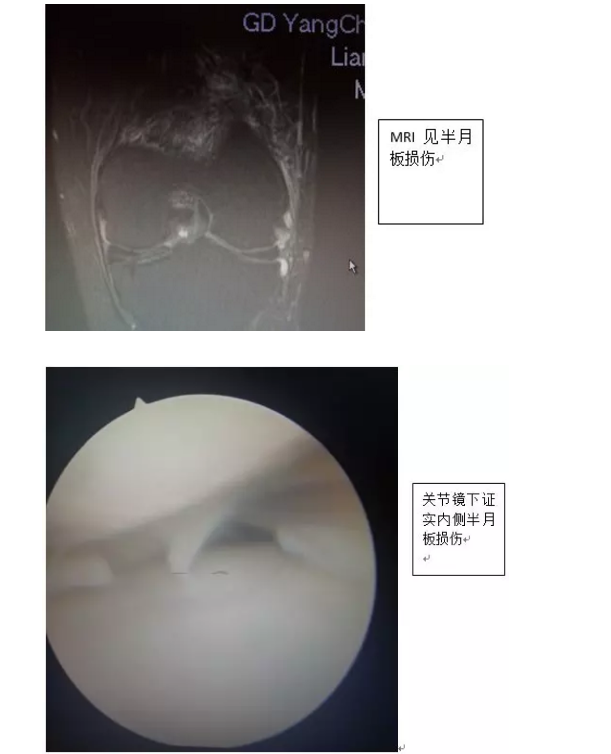

该患者梁某是一名50余岁男性,因膝关节外伤后疼痛一个月余到我院骨二科住院。患者入院后进行体查,膝关节MRI诊断为“膝关节半月板损伤”。经骨二科医师团队综合评估后,决定行膝关节镜检+半月板修补术治疗。术后患者康复良好,术后第二天即可下地负重行走,膝关节疼痛消失,一周后顺利出院,恢复正常生活。现患者为表达其感激之情,特意给医护人员送来锦旗。

膝关节镜技术具有手术切口小、出血少、手术损伤小、术后康复快等优点,大部分关节疾患都可关节镜治疗。